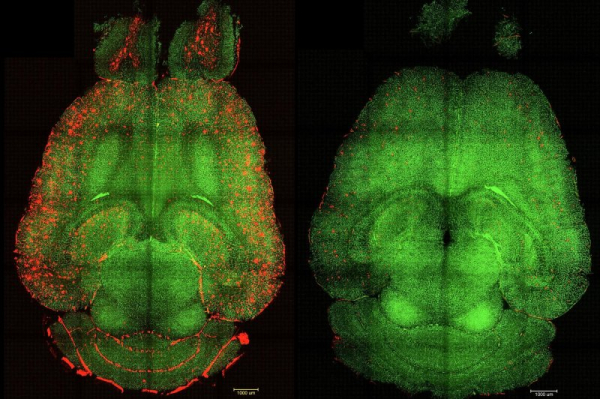

1 of 2 | Before-and-after fluorescence microscope images of a mouse brain show red-colored build-ups of toxic amyloid beta plaque (L) and the same brain 12 hours after being treated with nanoparticles. Spanish and Chinese scientists say their nanoparticle experiments could create a new focus on the blood-brain barrier in treating Alzheimer’s disease. Image courtesy Institute for Bioengineering of Catalonia

Only one hour after a series of nanoparticle injections, “we observed a reduction of 50%-60% in Amyloid beta amount inside the brain,” the authors stated, adding that the subject mouse — which was the equivalent of 90 years old in human terms and had been genetically programmed for high levels of amyloid beta — exhibited normal behavior six months after treatment, including a reversal of cognitive and memory decline.